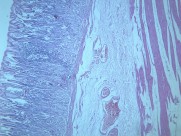

慢性萎缩性胃炎大全(12)张

本病以胃粘膜萎缩变薄,粘膜腺体减少或消失,并伴有肠上皮化生,固有膜内多量淋巴细胞、浆细胞浸润为特点。本性胃炎的病因比较复杂,部分可能与吸烟酗酒和用药不量有关,部分由慢性浅表性胃炎迁移发展而来,还有部分属兔自身免疫疾病。